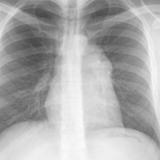

Case 8a Thymoma PA

Date: 03/27/2009

Views: 9452